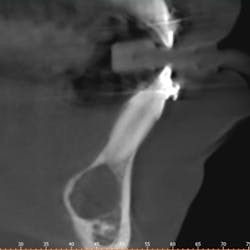

Clinically, there was no buccal or lingual expansion (figure 1). The patient’s medical history was noncontributory. A CT scan revealed a 1.5 cm x 1 cm well-defined, circular, hypodense area inferior to the lower incisors (figures 2–4).